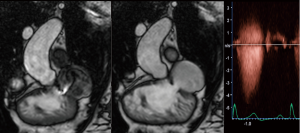

Current guidelines (4,8) recommend a standardized echocardiographic protocol in TOF patients. The precise evaluation of PR—a universal finding—and the main driver of RV dilatation and dysfunction, is essential. Theoretically, PR may be quantified with the same methods as aortic regurgitation. Proposed values for severe regurgitation include an effective regurgitant orifice area (EROA) greater than 115 mm2, regurgitant volume >115 mL, pressure half time <100 ms, a PR index <0.77, jet width >65% of the right ventricular outflow tract (RVOT) width, and diastolic flow reversal in PA branches (Figure 2) (11); however, these values are not robust and in clinical practice there is no widespread accepted method for quantifying PR with TTE. Furthermore, RV dilatation, the functional consequence of PR, is sensible but not specific for severe PR (12). For these reasons, grading PR severity by TTE remains challenging. Furthermore, while PR is the most common valvulopathy, other frequent findings are functional tricuspid regurgitation, aortic regurgitation, and residual pulmonary or subpulmonary stenosis.

CMR is the gold standard for blood flow measurements, particularly quantification of regurgitant volume in PR. The phase contrast sequence provides measurement of anterograde and retrograde flow to establish regurgitant fraction and establish PR severity (8) (Figure 5). A regurgitant fraction >40% is considered severe. Phase contrast also permits assessment of aortic regurgitation, and in patients with residual shunts, estimation of pulmonary-to-systemic blood flow (Qp:Qs) (25) (Figure 6) However, aortic or tricuspid regurgitation, common in TOF, limits the use of this technique.